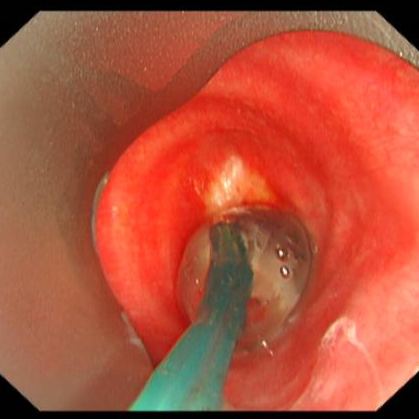

经过术前的充分准备,患者在全麻下,用可弯曲支气管镜引导插入法插入硬镜,通过高频电刀放射状切开狭窄环,再予气道球囊扩张器扩张气道置入硅酮支架,并置入喉罩复苏,最后成功为患者实施硬质支气管镜技术。术后,患者气道通畅,无呼吸困难、气促等症状出现,对比术前生活质量得到明显改善。

球囊扩张气道

患者术后情况